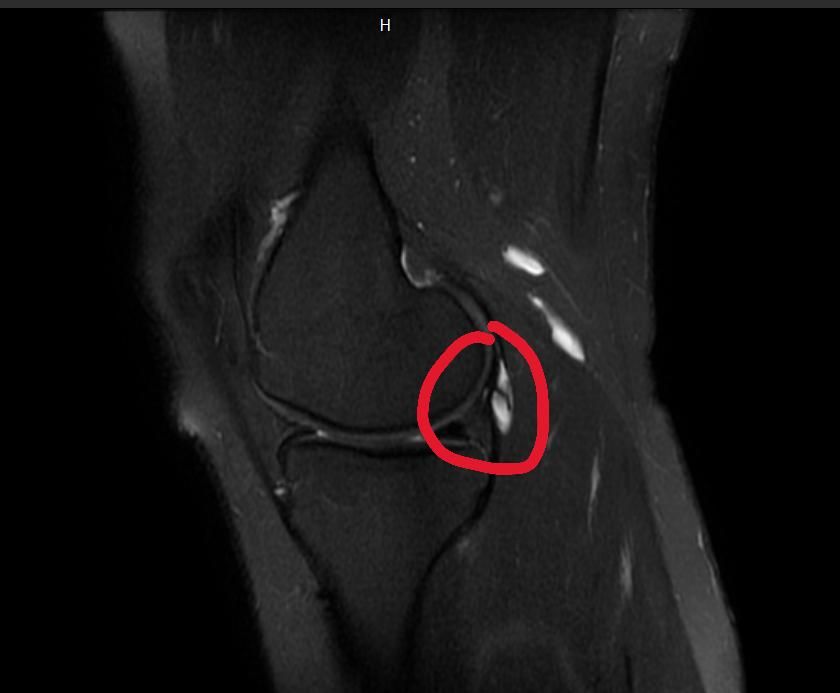

집에서 mri파일을 보면서 갈라져 보이는 흰색을 발견했는데 무릎에 별 영향은 없는 건가요??

올려주신 한 장의 컷만으로 단정할 수는 없지만, 표시하신 흰색 구조는 파열된 힘줄로 보일 가능성은 낮습니다. T2 계열 MRI에서는 물 성분이 밝게 보이는데, 관절액이 주머니처럼 고이거나 힘줄·인대 주변에 생긴 소량의 액체가 저렇게 보이는 경우가 흔합니다. 대표적으로 경미한 관절삼출, 인대 주위 액체, 작은 활액낭염이나 아주 작은 낭종(ganglion, parameniscal cyst 등)이 해당됩니다.

사진에서 보이는 갈라진 듯한 흰색은 꼭 병적인 파열이라기보다는 관절액(물), 혈관, 촬영 각도나 단면 때문에 그렇게 보이는 정상 구조인 경우가 많아요. MRI는 단면 사진이라 집에서 보면 실제보다 찢어진 것처럼 착시가 생기기도 해요. 그래서 의사가 전체 컷을 다 보고 정상이라고 한 거라면 연골·반월상연골 파열 같은 큰 문제는 없다는 의미일 가능성이 큽니다.

무릎 MRI상 정상이라고 해서 통증 및 부종이 없다고 보기는 힘들며, MRI촬영 방식에 따라서 관절액 또는 혈관의 단면 혹은 지방 연골표면이 반사된 것일 수 있습니다.

MRI는 무릎의 전반적인 구조물을 확인할 수 있으며, 조직의 성질에 따라서 흰색과 검은색으로 달리 보일 수 있습니다.

사진만으론 정확히 판단 할 순 없지만 해당 표시된 부분은 지방 또는 관절액, 염증으로 볼 수 있습니다.